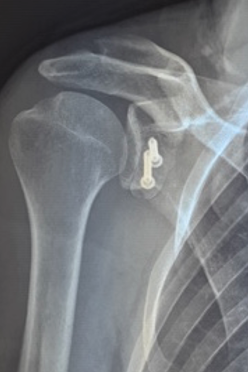

- la butée coracoïdienne (ou intervention de Latarjet) : il s’agit d’un transfert de la coracoïde (os de l’omoplate) en avant de la glène. Celle-ci est alors fixée à la glène par des vis le temps de la consolidation osseuse. Les vis non gênantes sont la plupart du temps laissées en place,

La butée coracoïdienne